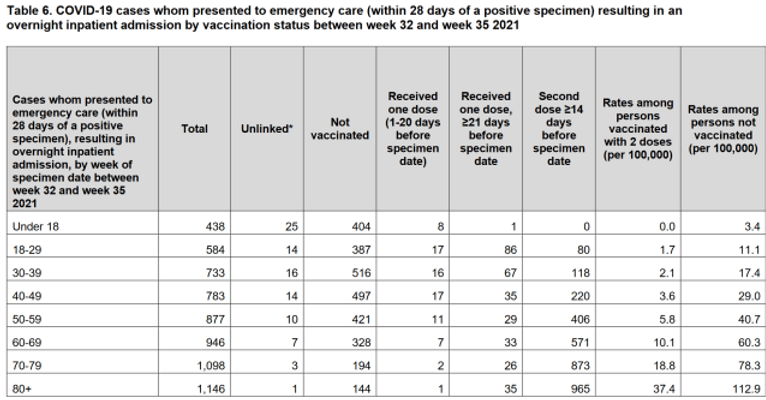

The following table is taken from Public Health England’s ‘Covid-19 Vaccine Surveillance Report – Week 36 – 2021‘, and it shows that between week 32 and week 35 of 2021 (when theoretically the so-called Delta variant was the dominant variant even when a purified isolate does NOT exist) there were just 404 Covid-19 hospitalizations recorded among the under 18’s in England.

Source – Page 17 – https://assets.publishing.service.gov.uk/government/uploads/system/uploads/attachment_data/file/1016465/Vaccine_surveillance_report_-_week_36.pdf

This number of hospitalizations among under 18’s is typical for most of the weekly reports, so why on earth are Covid-19 hospitalizations now as high as 1,132 among children?

We know that children have never been at high risk of suffering severe disease due to Covid-19, and everyone should know by now that a person could be hospitalized with a broken leg and classed as a Covid-19 hospitalization if they happen to test positive for Covid-19 with a highly questionable test within 28 days of admittance.

But we also know that the UK Government and NHS are attempting to justify Professor Chris Whitty’s decision to overrule the Joint Committee on Vaccination and Immunization and offer the Covid-19 vaccines to children. So what is this all about?

Are we seeing the UKHSA manipulate figures here through mass testing of already hospitalized children, to give the impression that experimental Covid-19 vaccination would benefit children?

When we include children in the hospitalization figures we find that the vaccinated population accounted for 75% of all Covid-19 hospitalizations between the 24th of January and the 20th of February, 2022. But when we remove children, we find that the vaccinated population accounted for 85% of all Covid-19 hospitalizations among over 18’s in England.